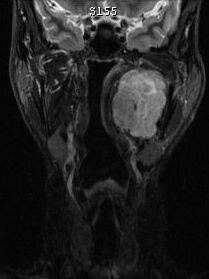

| Neurinom | 26-jährige Frau mit einem Tumor am linken Oberarm. Makroskopisch 45mm großes gekapseltes Gewebsstück mit rötlich-gelblichen weich-elastischen Schnittflächen. Mikroskopisch: Bekapselten spindelzelligen Tumor. Kein Nachweis von Kernatypien oder vermehrten Mitosen. Eingelagert sind ektatische, teilweise thrombosierte Blutgefäße mit Einblutungen und Blutungsresiduen in Form von Hämosiderophagen. Immunhistologisch positiv mit S100. CD34, Alpha Aktin, Caldesmon und CD 68 negatic. Die proliferative Aktivität ist nicht erhöht. Benigner, peripheren Nervenscheidentumor, Neurinom. ![]() |

![]() |